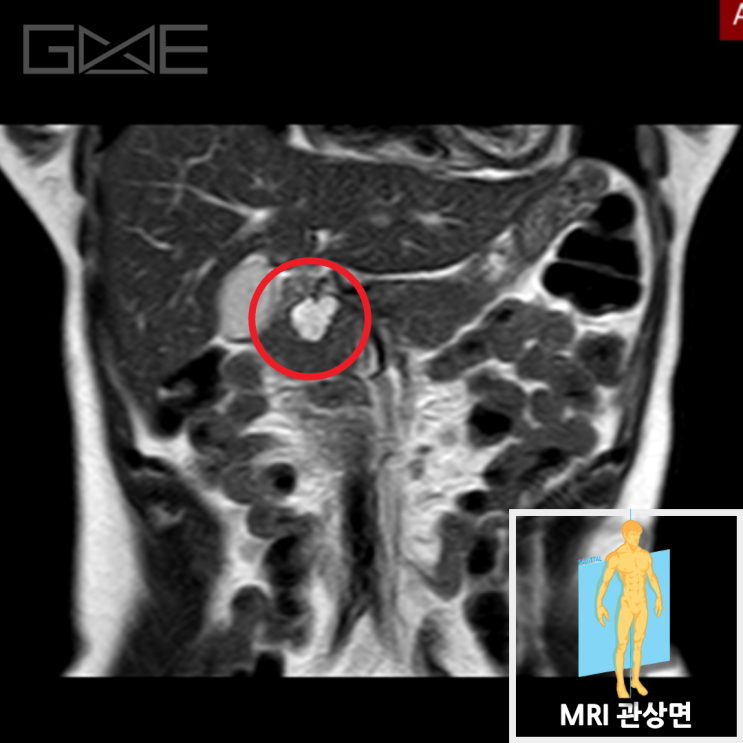

MRI상 췌장 갈고리돌기(uncinate process) 쪽으로 2cm 크기의 저신호 결절이 관찰되었습니다. 이 병변은 MRI 확산강조 영상에서는 고신호로 보여, 악성을 시사하였습니다. 확산강조 영상에서 고신호를 보이는 이유는 종양 내 세포의 밀도가 높아져 물질의 확산이 감소하기 때문입니다. 이러한 소견은 췌장암 진단을 뒷받침합니다.

한마디: 췌장암 진단. MRI와 확산강조 영상 소견상 악성 종양이 확인되어, 추가적인 치료를 위해 상급병원으로 신속히 전원하였습니다. 췌장암은 조기 발견 및 적절한 치료가 매우 중요합니다.

• 췌장MRI: 갈고리돌기(uncinate process) 쪽 2cm 저신호 결절 췌장MRI: 갈고리돌기(uncinate process) 쪽 2cm 저신호 결절